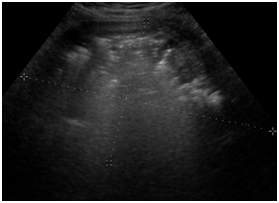

Patients Chest X-ray revealed normal findings. Pelvic ultrasound (Figure 1) showed enlarged uterus 16.9 cm x 10.59 cm x 4.95 cm with heterogeneity compatible with a history of multiple large leiomyomas. There were multiple dirty shadows with ring down densities suggestive of air within the uterine parenchyma. A loculus of fluid within the uterus was also noted (Figure 1). Abdominal CT imaging (Figure 2) (Figure 3) confirmed an enlarged lobular uterus. There were heterogenous multilobular masses with decreased attenuation and numerous foci of internal gas. Findings were most consistent with a necrotic fibroid, lesion measured 20 x 11.4cm. Gas was present within the lesion anteriorly and findings consistent with fluid rather than soft tissue density seen within the adjacent portions of the lesion (Figure 2) (Figure 3). No free intraperitoneal air was noted. Patient was soon after admitted to the Gynecology service with a diagnosis of Pyomyoma.

Figure 1 Patient Number 1, Transvaginal Ultrasound: enlarged uterus 16.9 cm x 10.59 cm x 4.95 cm with heterogeneity compatible with a history of multiple large leiomyomas.